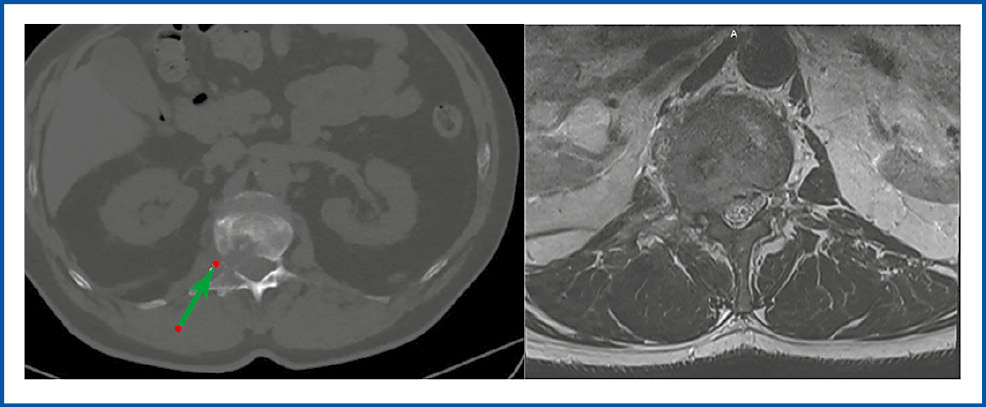

По данным КТ и МРТ поясничного отдела позвоночника определяется очаг литической деструкции в теле правой половины позвонка LI, заполняющий правую половину тела с переходом на правую боковую дужку, с компрессией корешка LI справа (рис. 5).

Рис. 5. КТ и МРТ поясничного отдела позвоночника больной Н. в аксиальном срезе до лечения (стрелкой указана компрессия нервного корешка).

Fig. 5. Axial view of CT and MRI of the lumbar spine of the patient N. before treatment (arrow indicates compression of the nerve root).